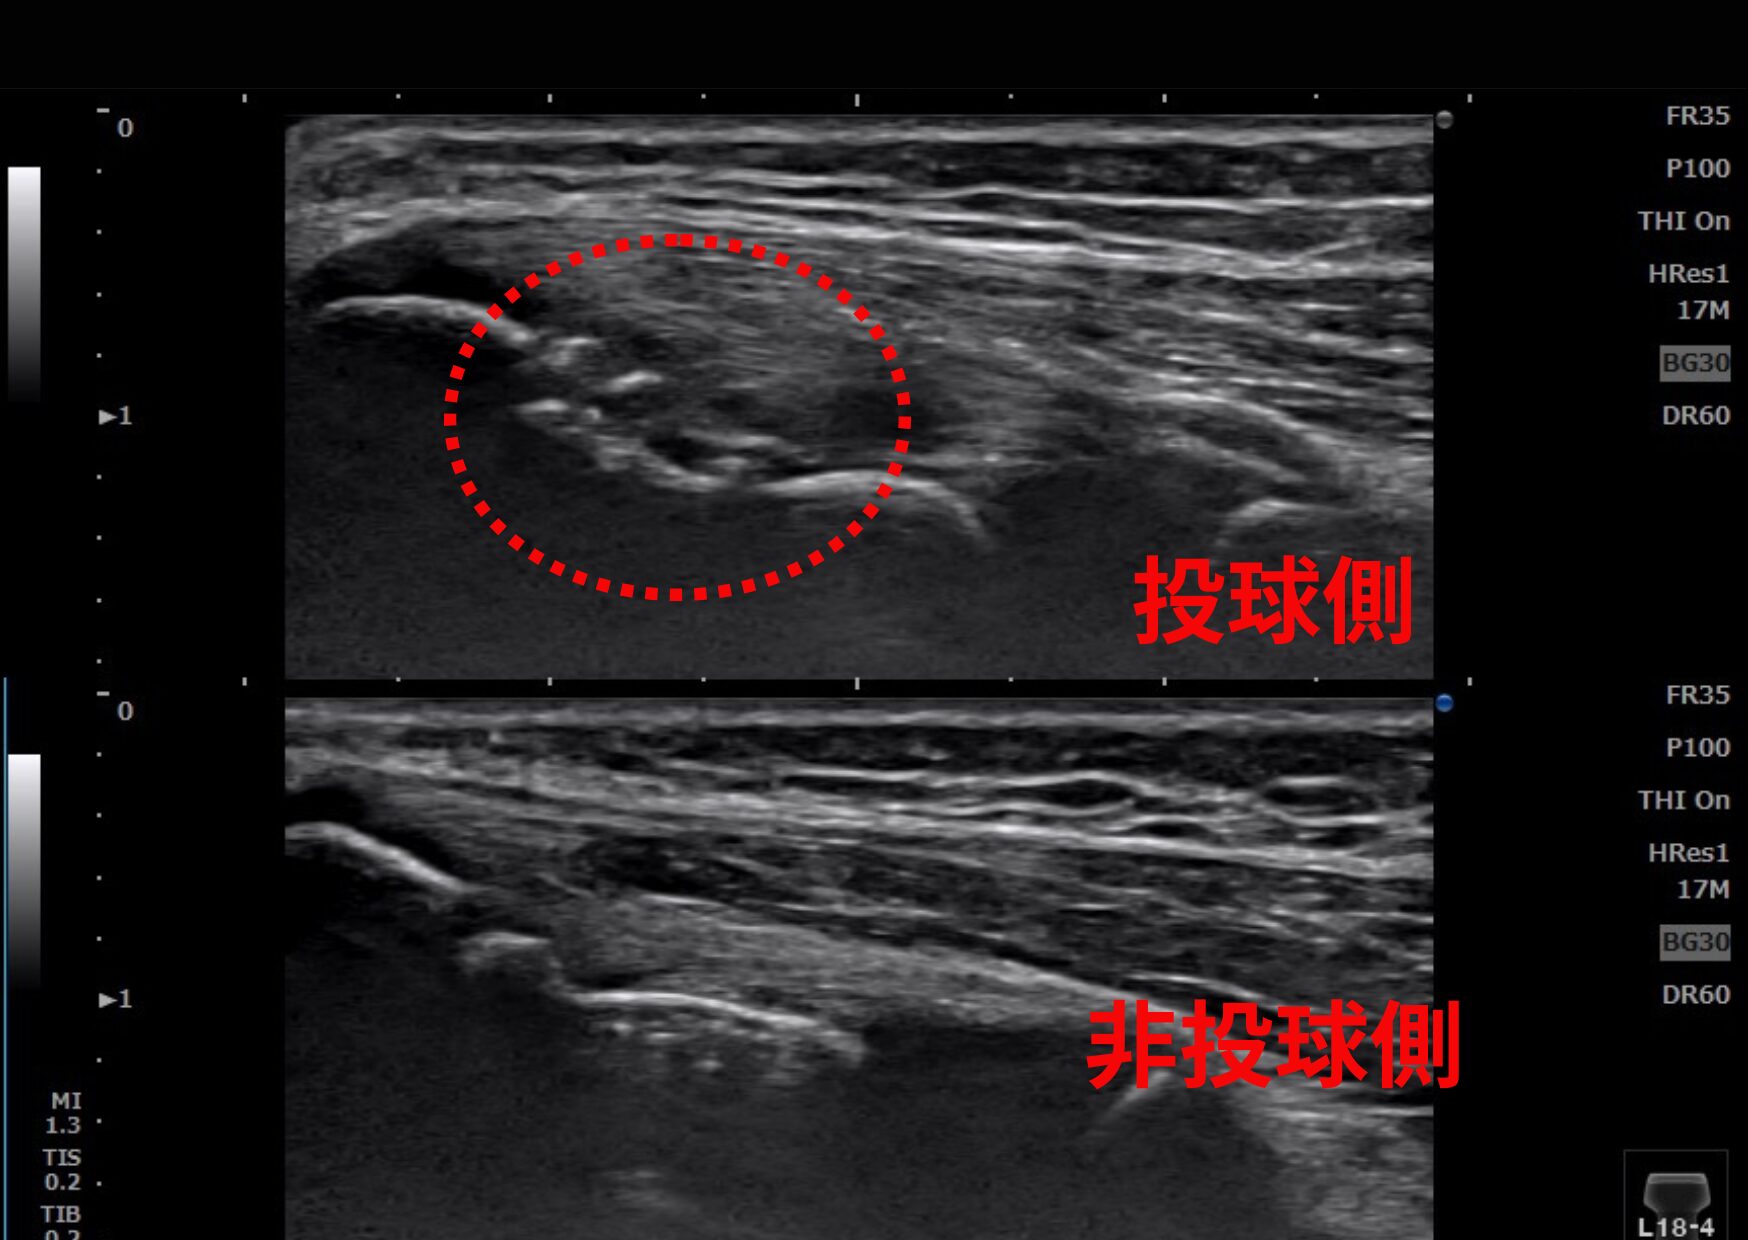

当院のこだわり:極めて鮮明な解像度

当院が採用しているプローブは、怪我の多い「表層3〜4cm」の状態を驚くほど鮮明に映し出す特殊仕様(コニカミノルタ L18-4)です。微細な肉離れや、レントゲンでは見逃されがちな軟骨の損傷も正確に捉えます。

Case 01:野球肘(内側上顆骨折)

「あ、やばい」と思ったその1球。

野球肘・内側上顆骨折のエコー画像

▲ エコーで捉えた内側上顆(骨端核)の損傷。微細な骨の連続性の不全を可視化しています。

中学生の野球選手。投球中にはっきりと「痛めた瞬間」を覚えているケースでした。この記憶がある場合は急性外傷の可能性が高いため、即座に精密検査が必要です。

【エコー所見】

内側上顆(成長期特有の骨端核部分)の損傷を可視化。骨の不整や、周囲の炎症反応を客観的に評価しました。